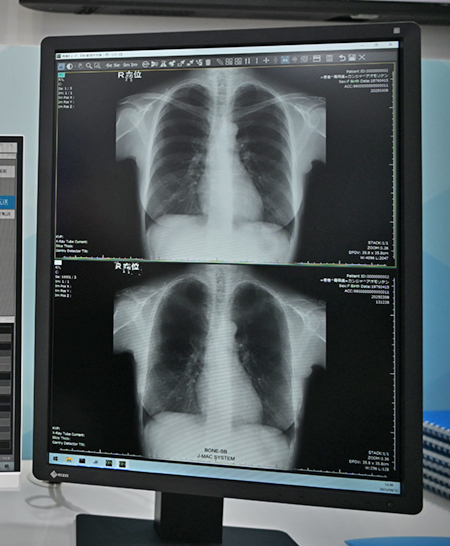

肋骨減弱は胸部単純X線画像で高吸収域となる肋骨を減弱処理して,骨と重なる結節などの病変候補の視認性を向上させる。装置メーカー,機種を問わず,胸部単純X線画像であれば,適用することが可能だ。これにより読影しやすい画像を提供でき,画像診断業務の効率化,医師の負担軽減を図れる。また,見落としのリスクも低減でき,高精度な診断にも寄与する。

「iRad-QA」に標準搭載される「肋骨減弱」機能(画面下が減弱処理ずみの画像)はAI技術で骨と重なる結節などの視認性を向上